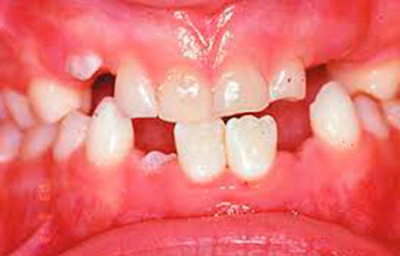

Современные методы терапии у детей

Обычно пародонтит встречается у детей не раньше 9–10 лет, причиной становится неправильный прикус или короткая уздечка верхней губы. Чтобы лечение было эффективным, устраняют первопричину.

Терапия включает применения комплекса из противовоспалительных препаратов, промывания, полоскания, физиотерапии.

Дополнительно назначаются витамины, минералы, иммуностимуляторы и противоаллергические средства.